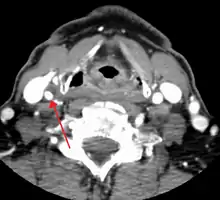

CT image of a 70 percent stenosis of the right internal carotid artery

One of several different imaging modalities, such as a computed tomography angiogram (CTA)[12][13][14] or magnetic resonance angiogram (MRA) may be useful. Each imaging modality has its advantages and disadvantages - Magnetic resonance angiography and CT angiography with contrast is contraindicated in patients with chronic kidney disease, catheter angiography has a 0.5% to 1.0% risk of stroke, MI, arterial injury or retroperitoneal bleeding. The investigation chosen will depend on the clinical question and the imaging expertise, experience and equipment available.[15]